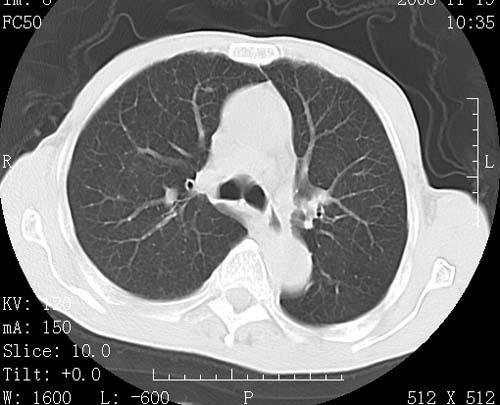

术前查体,双肺部结节是转移?结核?请点评

转移 隆突下淋巴结亦肿大

首先考虑转移,纵隔内淋巴结亦肿大;

1)符合食管癌表现。2)两肺及纵隔淋巴结多发性转移瘤。3)左肺上叶舌段及两肺下叶炎症感染。

食管癌伴双肺转移,评述:肺部毛细血管网丰富,全身血液均快速流经肺部,癌细胞容易过滤定植,形成转移瘤,影象特点为以毛细血管末梢为中心的结节灶,边缘光滑锐利,少见有中心空洞着,不同来源的转移瘤可有各自特点,如甲状腺癌为双肺弥漫性微结节,本例有原发灶,双肺影象灶典型,左肺舌段条带状网格样伴胸膜天幕征,可视为癌性淋巴管炎。